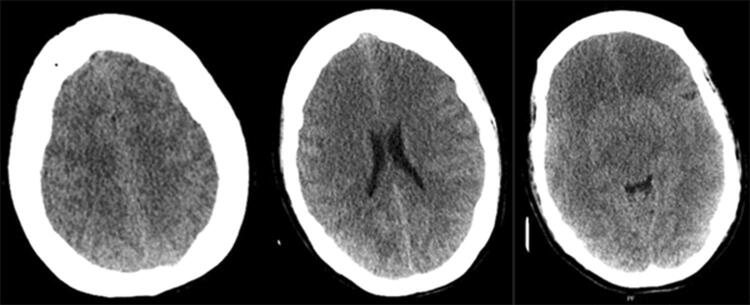

A 49-year-old patient was admitted to a hospital due to abdominal pain. A gastric-by-pass operation had been performed eight years before this admission, and afterwards the patient developed an anorexic behavior and a severe malnutrition, resulting in the loss of 100 kg. Seven days prior to admission to the local hospital the patient terminated oral intake and was brought to the hospital by relatives. Body weight at admission was 145 kg, the patient was considered severely malnutritioned and was admitted to a surgical ward due to abdominal pain. Bilateral leg swelling was present, and s-albumin was 8 mg/L. Parenteral nutrition as well as enteral nutrition was started with 1800 kcal/day, and albumin was administrated. After three days the patient developed a stiff neck and decreased consciousness. Lumbar puncture was performed with no abnormal findings. Due to suspected septicemia antibiotics was started. The patient’s consciousness continued to decrease and intubation was necessary, hence the patient was referred to the local ICU. Caloric intake was reduced, and phosphate was administered. The next day the patient developed fasciculations in left hand, left part of the face, and anisocoria. A computed tomography (CT) scan was performed which revealed cerebral edema (Fig. 1). The patient was admitted to our university hospital.

Fig. 1.

Initial CT scan showing general cerebral edema